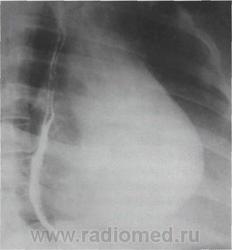

В правой передней косой проекции определяются ранние и самые выразительные признаки увеличения левого предсердия. При этом тень сердца проступает в ретрокардиальное пространство, частично или полностью занимая его, или даже накладываясь на тень позвоночника.

По мере увеличения левого предсердия пищевод, тесно прилегающий к его задней стенке, отклоняется кзади и вправо. Степень уменьшения ретрокардиаль - ного пространства, протяженность дуги и ее радиус воспроизводят форму левого предсердия и позволяют судить о степени его увеличения. При чистом или преобладающем митральном стенозе отклонение пищевода происходит по дуге малого радиуса.

Рентгенологические признаки дилатации левого предсердия в правой косой проекции с контрастированным пищеводом: а, б, в - I, II и III степени увеличения левого предсердия.

В норме ретрокардиальное пространство на уровне левого предсердия составляет не менее 3 см. При первой степени увеличения левого предсердия ретрокардиальное пространство сужено до половины. При второй степени контрастированный пищевод располагается уже в задней половине ретрокарди - ального пространства. При третьей степени тень сердца и контрастированный пищевод накладываются на тень позвоночника .

Заметно все большее отклонение контрастированного пищевода кзади и сужение ретрокардиального пространства.